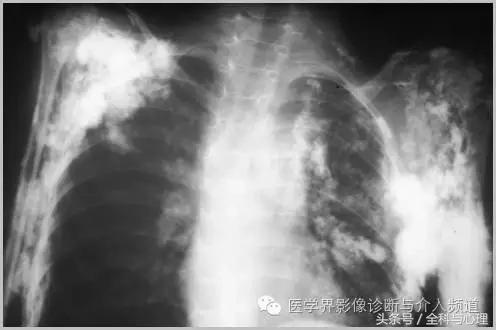

1、全身性钙质沉着症:皮肤、皮下或深部结缔组织钙化,与多种代谢紊乱及胶原血管病变有关,如皮肌炎,看起来像异位骨化,但没有真正的骨形成。开始为浅表的结节状或斑块状钙化,逐渐向更深的组织发展,表现为关节周围大片状钙化灶。

皮肌炎